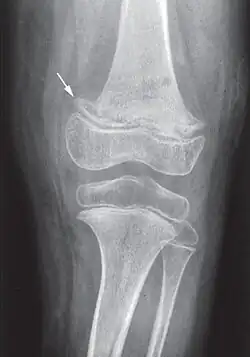

Radiographie d'un genou scorbutique. La flèche indique le départ d'une « ligne scorbutique » : bande très dense séparée de la diaphyse par une étroite zone claire non homogène.

Les douleurs osseuses sont liées aux hémorragies sous-périostées. La radiographie peut montrer les troubles du périoste (hématomes sous-périostés) et de la structure osseuse (ostéoporose avec aspect en « verre pilé », la « ligne scorbutique » séparant la diaphyse des extrémités, élargissement de l'extrémité antérieure des côtes...)[23].